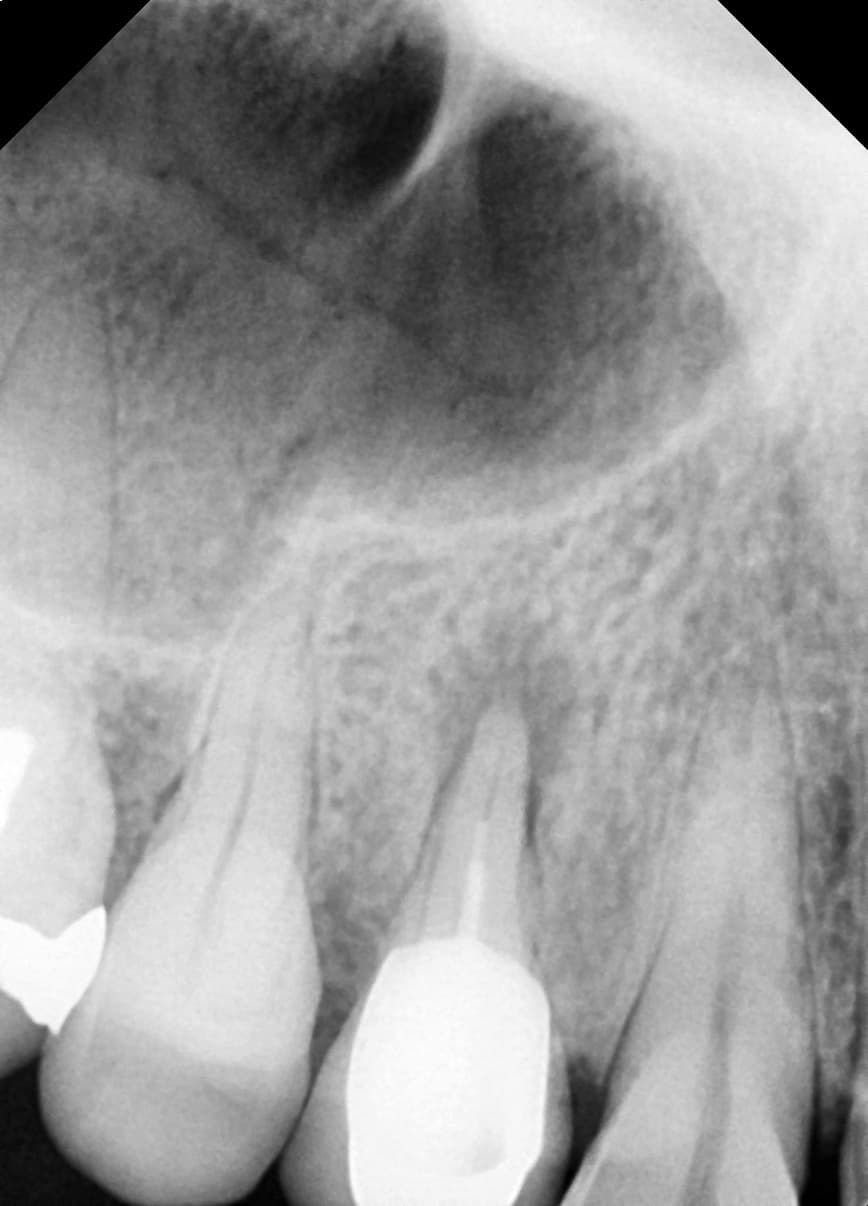

Periapical Lesion Healed

Molar with severe inflammation and pus

Before

After

Complete healing of periapical lesion 6 months after treatment